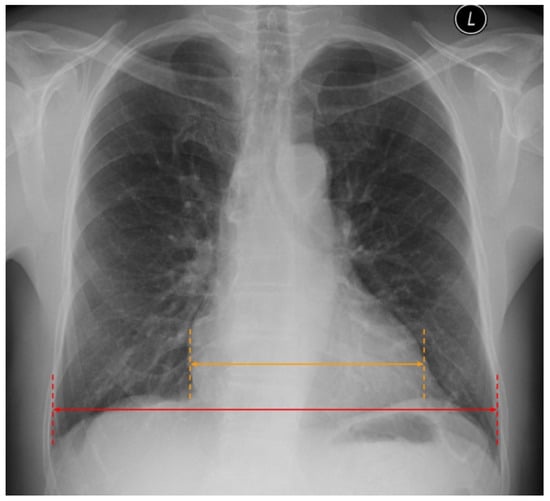

2. Chest X-ray

2.2. Cardiac Abnormalities Related to HF in CXR